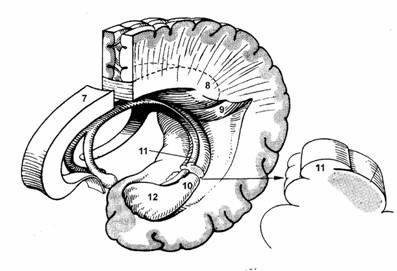

Ábra. 27, bal hippocampus

7. kérgestest

8. henger

9. hippocampus

10. hippocampus

11. fringe

12. Leg